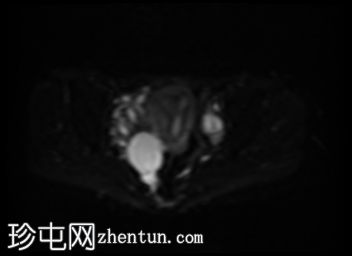

轴向

DWI

此外,所有囊肿均未显示弥散受限或实性成分强化。

本例卵巢囊肿呈中等 T1 信号,类似于肌肉信号,T2 信号高,伴有薄内隔和外周壁强化。但无内部强化或弥散受限。STIR 序列显示与 T2 一致的信号,无任何脂肪成分。该表现提示卵巢出血性囊肿处于早期或消退期。